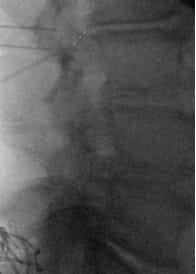

- Create an IPG pocket; tunnel leads from the inferolateral tension-relief loop pocket to the IPG pocket; test impedances and motor responses again with the IPG in the IPG pocket.

- Form tension-relief loops without sharp bends or significant friction points; tuck the loop into the tension-relief loop pocket.

- Irrigate, close with layered sutures, and apply adhesives and dressing.